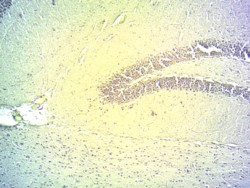

Immunohistochemistry Cryo-sectioned Mouse Brain (Hippocampus) shows staining in the granular layer of the dentate gyrus. Recommended concentration